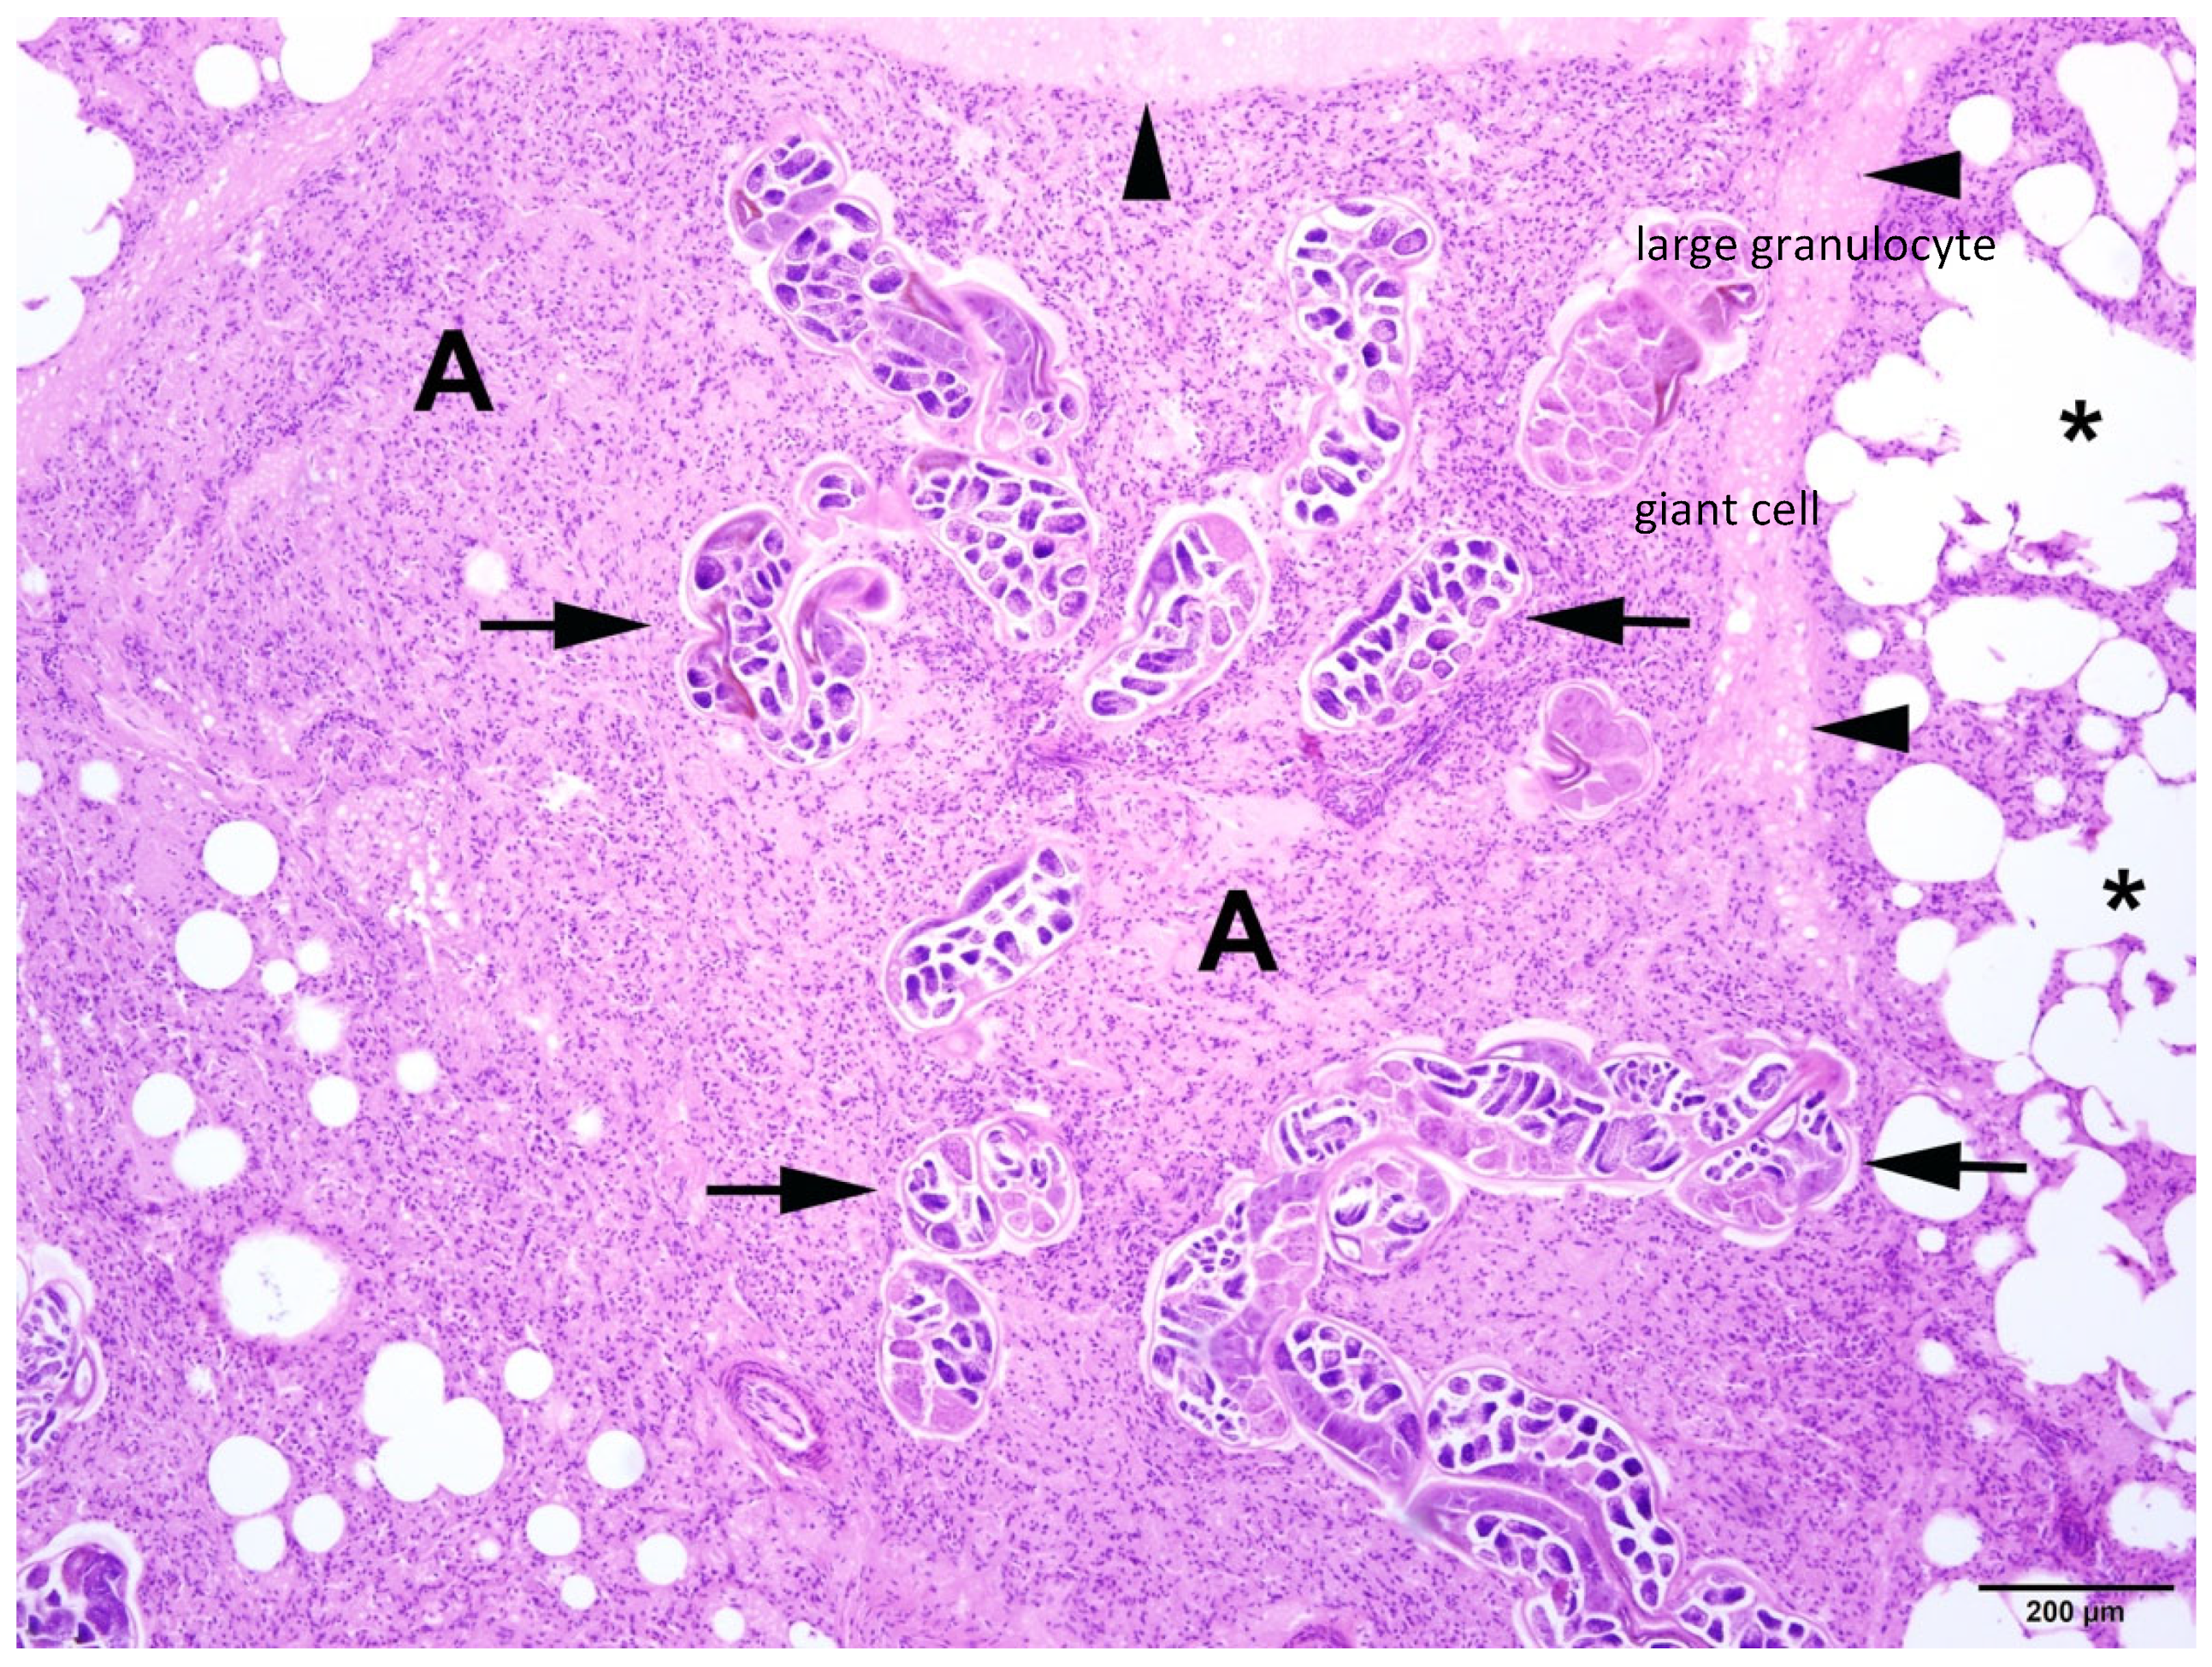

In all animals with respiratory parasitic infections, bronchopneumonia or pneumonia was detected. Several types of inflammation could be diagnosed, including catarrhal-purulent or -haemorrhagic, granulomatous-necrotising, purulent-necrotising, and alveolar-interstitial. In most cases, pathological changes included several types of inflammatory lesions within the same animals (Figure 7 and Figure 8).

Figure 7.

Harbour seal, lung: severe pulmonary endoparasitosis with nematodes in the parenchyma (arrows) associated with lobular atelectasis (A). Additionally, there is a moderate interstitial oedema (arrowheads) and an alveolar emphysema in the adjacent pulmonary tissue (asterisks). HE (4×).

Different severity grades of alveolar/interstitial pulmonary emphysema (pathological accumulation of gas in the alveoli and/or cell spaces) could be detected in 44 animals often associated with parasitic infection and bronchopneumonia (Figure 9). Pulmonary atelectasis (collapse of alveoli) was found in 21 individuals. In 46 animals, alveolar/interstitial pulmonary oedema (pathological fluid accumulation in the alveoli and/or cell spaces) was recorded, with alveolar oedema present in 37 animals.

Figure 9.

Harbour seal, lung: severe pulmonary endoparasitosis with nematodes in a bronchus (arrowhead) and in the parenchyma (arrows) with associated atelectasis. Adjacent pulmonary tissue displays alveolar emphysema (asterisks). HE (4×).